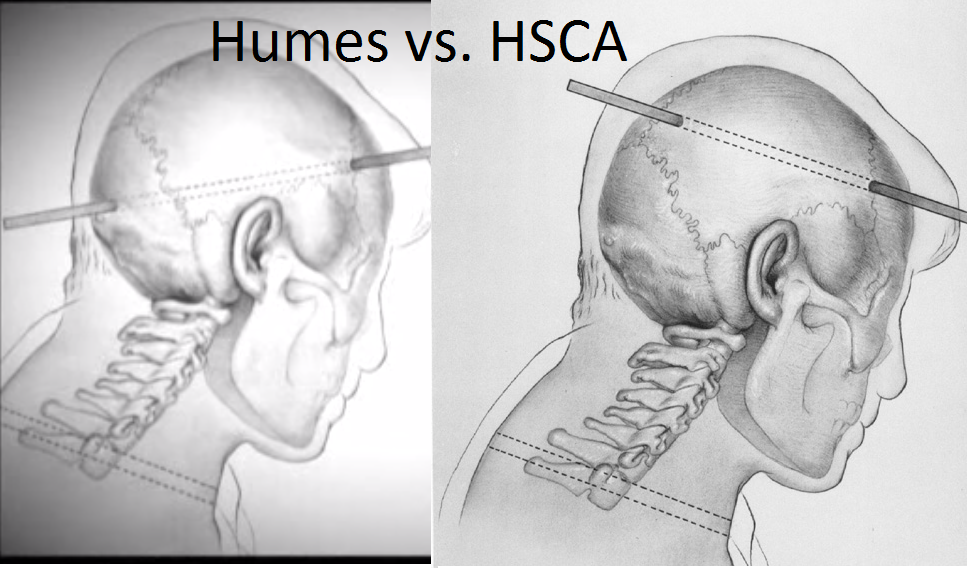

Massensuggestion. Weiter spricht für den Schuss von vorne (aus Richtung des Grashügels), dass dort stehende Passanten einen Schuss/mehrere Schüsse gehört haben (wollen). Dass sich so viele Menschen in genau diesem Moment geirrt haben sollen (aufgrund von Echos, Falschwahrnehmung, etc.) glaube ich einfach nicht.

BTW: Halte ich Dr. Cyril Wecht, der Kennedy u.A. auch autopsiert hat, für einen äußerst fähigen Menschen. Seine Aussagen, die die These des Schusses von vorn ebenfalls stützen, halte ich für

wissenschaftlich korrekt und verständlich wiedergegeben.